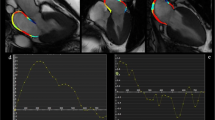

Imaging assessment of left atrial function. LA volumetric assessment using Transthoracic echocardiography (TTE) include biplane disk method (A) and 3D method(B), and using CMR include biplane area length method (C), and short axis stack method (D). LA deformation assessment using Speckle tracking echocardiography (E), and feature tracking on CMR (F). An example of LA strain curve and the measurements corresponding to LA phases (G). LAS_r = LA strain at reservoir, LAS_cd = LA strain at conduit, LAS_bp = LA strain at booster-pump phase

SR is myocardial deformity over time (the speed of myocardial deformation) [56]. Although LA strain (LAS) is preload dependent, loading has less effect on LA strain than LA volume [24], while LA strain rate (LASR) is less load-dependent than strain [57]. Both TTE and CMR use post-processing image analysis software to assess LAS and LASR, using routinely acquired 2-chamber and 4-chamber cine images. LA endocardial borders are manually traced and propagated throughout the cardiac cycle using speckle tracking in TTE or feature tracking in CMR (Fig. 2E and F).

Tissue Doppler imaging (TDI) is an image acquisition that is used traditionally to estimates strain in TTE. However, it depends on angle of insinuation and provides regional evaluation of LA function [58, 59]. STE technique is a post-processing algorithm that quantifies LA deformation by tracking the motion of speckles within the whole myocardium through the cardiac cycle, using standard 2D echocardiography B-mode images [60](Fig. 2E). Strain and SR curves are generated after tracing the LA endocardium during systole and diastole. It is recommended to use non-foreshortened views of the LA in order to obtain adequate strain values, as well as the use of ventricular end-diastole as the time reference frame of zero strain [61].

Feature tracking CMR

Feature tracking (FT) is a post-processing strain assessment technique that uses standard CMR cine images for strain analysis (Figs. 2F and G). The analysis is performed offline using dedicated software which provides a more practical way by allowing shorter scan times. The general principle of FT is similar to STE, where features within the myocardium are tracked through the cardiac cycle. Strain assessment by CMR has several advantages over TTE such as improved spatial resolution, high signal and contrast ratio (between blood pool and myocardium), unlimited windows and clearer myocardial definition, enabling optimal tracking. Furthermore, with adequate planning, there is less propensity for foreshortened images than TTE.

Similar strain curves are generated by both TTE and CMR techniques (Fig. 2G). LAS/LASR can be measured for the three LA phases [61]: reservoir function (LAS_r and LASR_r), conduit function (LAS_cd and LASR_cd) and contraction booster-pump ( LAS_bp and LASR_bp). LAS_cd can be calculated as: LAS_cd = LAS_r – LAS_bp.